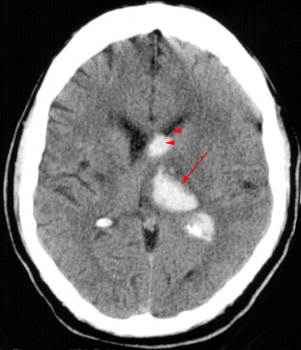

Head CT > Stroke > Intracerebral Hemorrhage

Intracerebral Hemorrhage

The most common cause of non-traumatic intracerebral hematoma is hypertensive hemorrhage. Other causes include amyloid angiopathy, a ruptured vascular malformation, coagulopathy, hemorrhage into a tumor, venous infarction, and drug abuse.